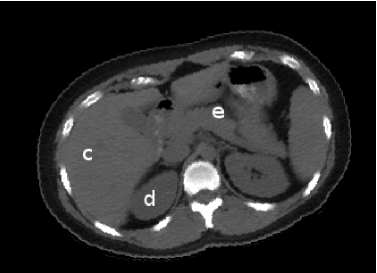

Figure 1 shows annotated landmarks for five different objects (skin, liver, right kidney, left kidney, spleen) in a CT slice of the abdominal region. Note that different number of landmarks are used for different objects considering their size.

![]() |